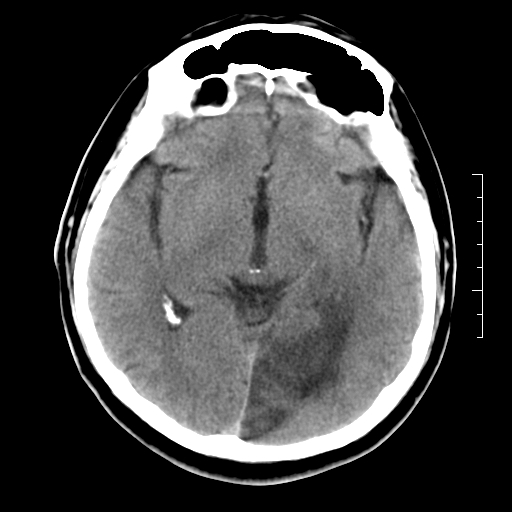

以下是引用随光逐影在2010-7-22 20:48:00的发言:[br]1)考虑左侧颞枕叶及左侧小脑脑梗塞。2)左侧半卵圆中心多发性腔隙性脑梗塞。[br]建议:必要时行mri检查。

以下是引用linyiming在2010-7-23 1:17:00的发言:[br])考虑左侧颞枕叶及左侧小脑脑梗塞。2)左侧半卵圆中心多发性腔隙性脑梗塞。[br]建议:必要时行mri检查。 [br]